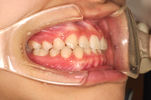

上顎前突(じょうがくぜんとつ)・出っ歯

主訴:出っ歯、がたがたが気になる

年齢:8y0m

診断:叢生を伴う上顎前突

装置・期間:

第一期治療 上下顎拡大装置(クアッドヘリックス・バイヘリックス)+バイオネーター 4年間(8y7m~12y7m)

第二期治療 上下顎マルチブラケット装置 2年5カ月間(12y8m~15y1m)

保定 上下顎保定装置 2年間以上

治療費:第一期治療 矯正基本料400,000円+処置料3,000~6,000円×33回(別途消費税)

第二期治療 矯正基本料400,000円+クリアブラケット代30,000円+処置料3,000~6,000円×28回(別途消費税)

保定装置料 55,000円(別途消費税)